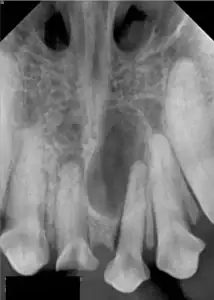

This is an X-ray of a lower jaw affected by a large cystic lesion, later diagnosed as originating from an unerupted tooth

The tooth causing the cyst has been removed and the cyst lining connected to the gum crerating a permanent hole depressurising the cyst and allowing the bone to reform